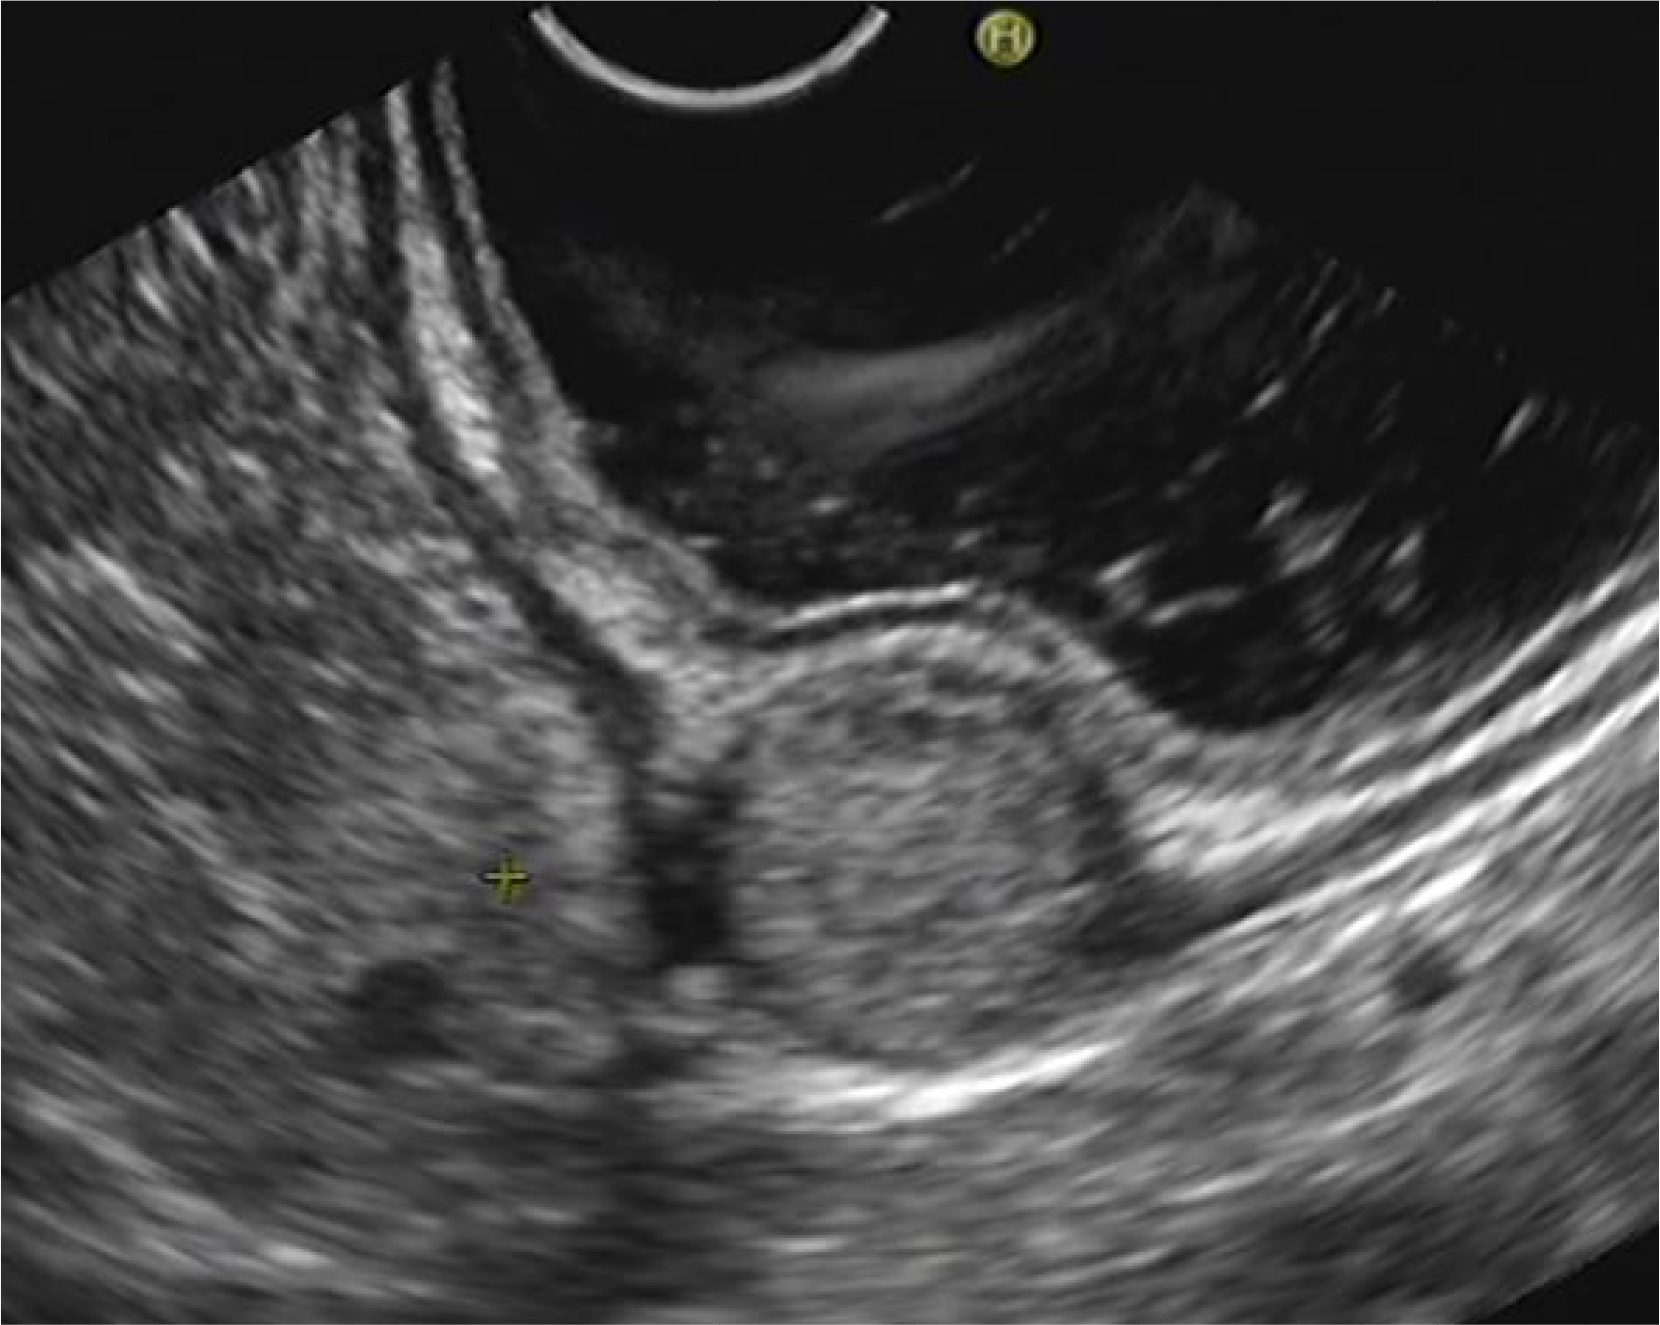

Ten patients received EUS. The EUS characteristics of 10 patients with gastric glomus tumors was presented in Table 1. Nine lesions were located in antrum and two tumors were found in the gastric body. All the lesions presented as a submucosal tumor and one lesion had an ulcer on its surface (Figure 1), leading to hemorrhage. The maximum size of tumors ranged from 10 to 35 mm with mean size being 19 mm. Nine lesions were from fourth layer, and one lesion was from third and fourth layers. Eight lesions were presented with mild-hyperechoic round or oval mass (Figure 2); one lesion was mild-hyperechoic oval mass with hypoechoic spots; one lesion was hypoechoic oval mass with a clear border. Ten patients with gastric GISTs located in gastric antrum, 10 patients with gastric leiomyoma located in gastric antrum. 10 patients with gastric schwannoma located in gastric antrum, and 10 patients with gastric ectopic pancreas located in gastric antrum were randomly selected. The EUS features of gastric glomus tumors were compared with that of gastric GISTs, leiomyoma, schwannoma, and ectopic pancreas, as shown in Table 2. The typical EUS feature of gastric glomus tumor is a triad: antrum; round or oval; mild-hyperechoic lesion from fourth layer.

Gastric glomus lesions presented with mild-hyperechoic round or oval mass